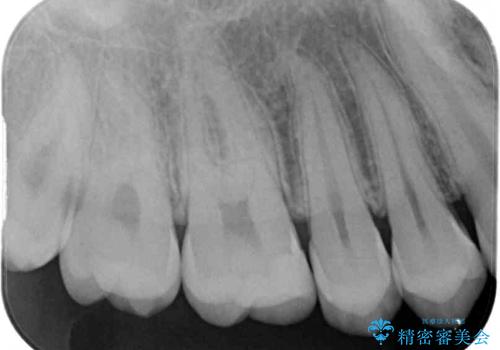

フロスが引っかかる セラミックインレーによるむし歯治療

- ウェブサイトの症例(https://seimitsushinbi.jp/case/9473/)を見て、同じようにフロスが引っかかるとのことで来院された患者様です。

虫歯を除去した後、セラミックインレーにて修復治療を行うこととしました。

セラミックインレー装着後はフロスの引っかかるストレスから解放され、患者様には大変満足していただきました。